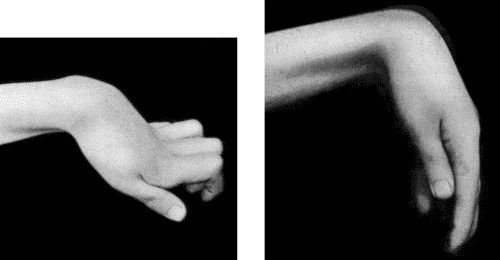

| 90. | Drop-Wrist following Fracture of Shaft of Humerus | 365 |

| 91. | To illustrate the Loss of Sensation produced by Division of the Median Nerve | 367 |

| 92. | To illustrate Loss of Sensation produced by Complete Division of Ulnar Nerve | 368 |